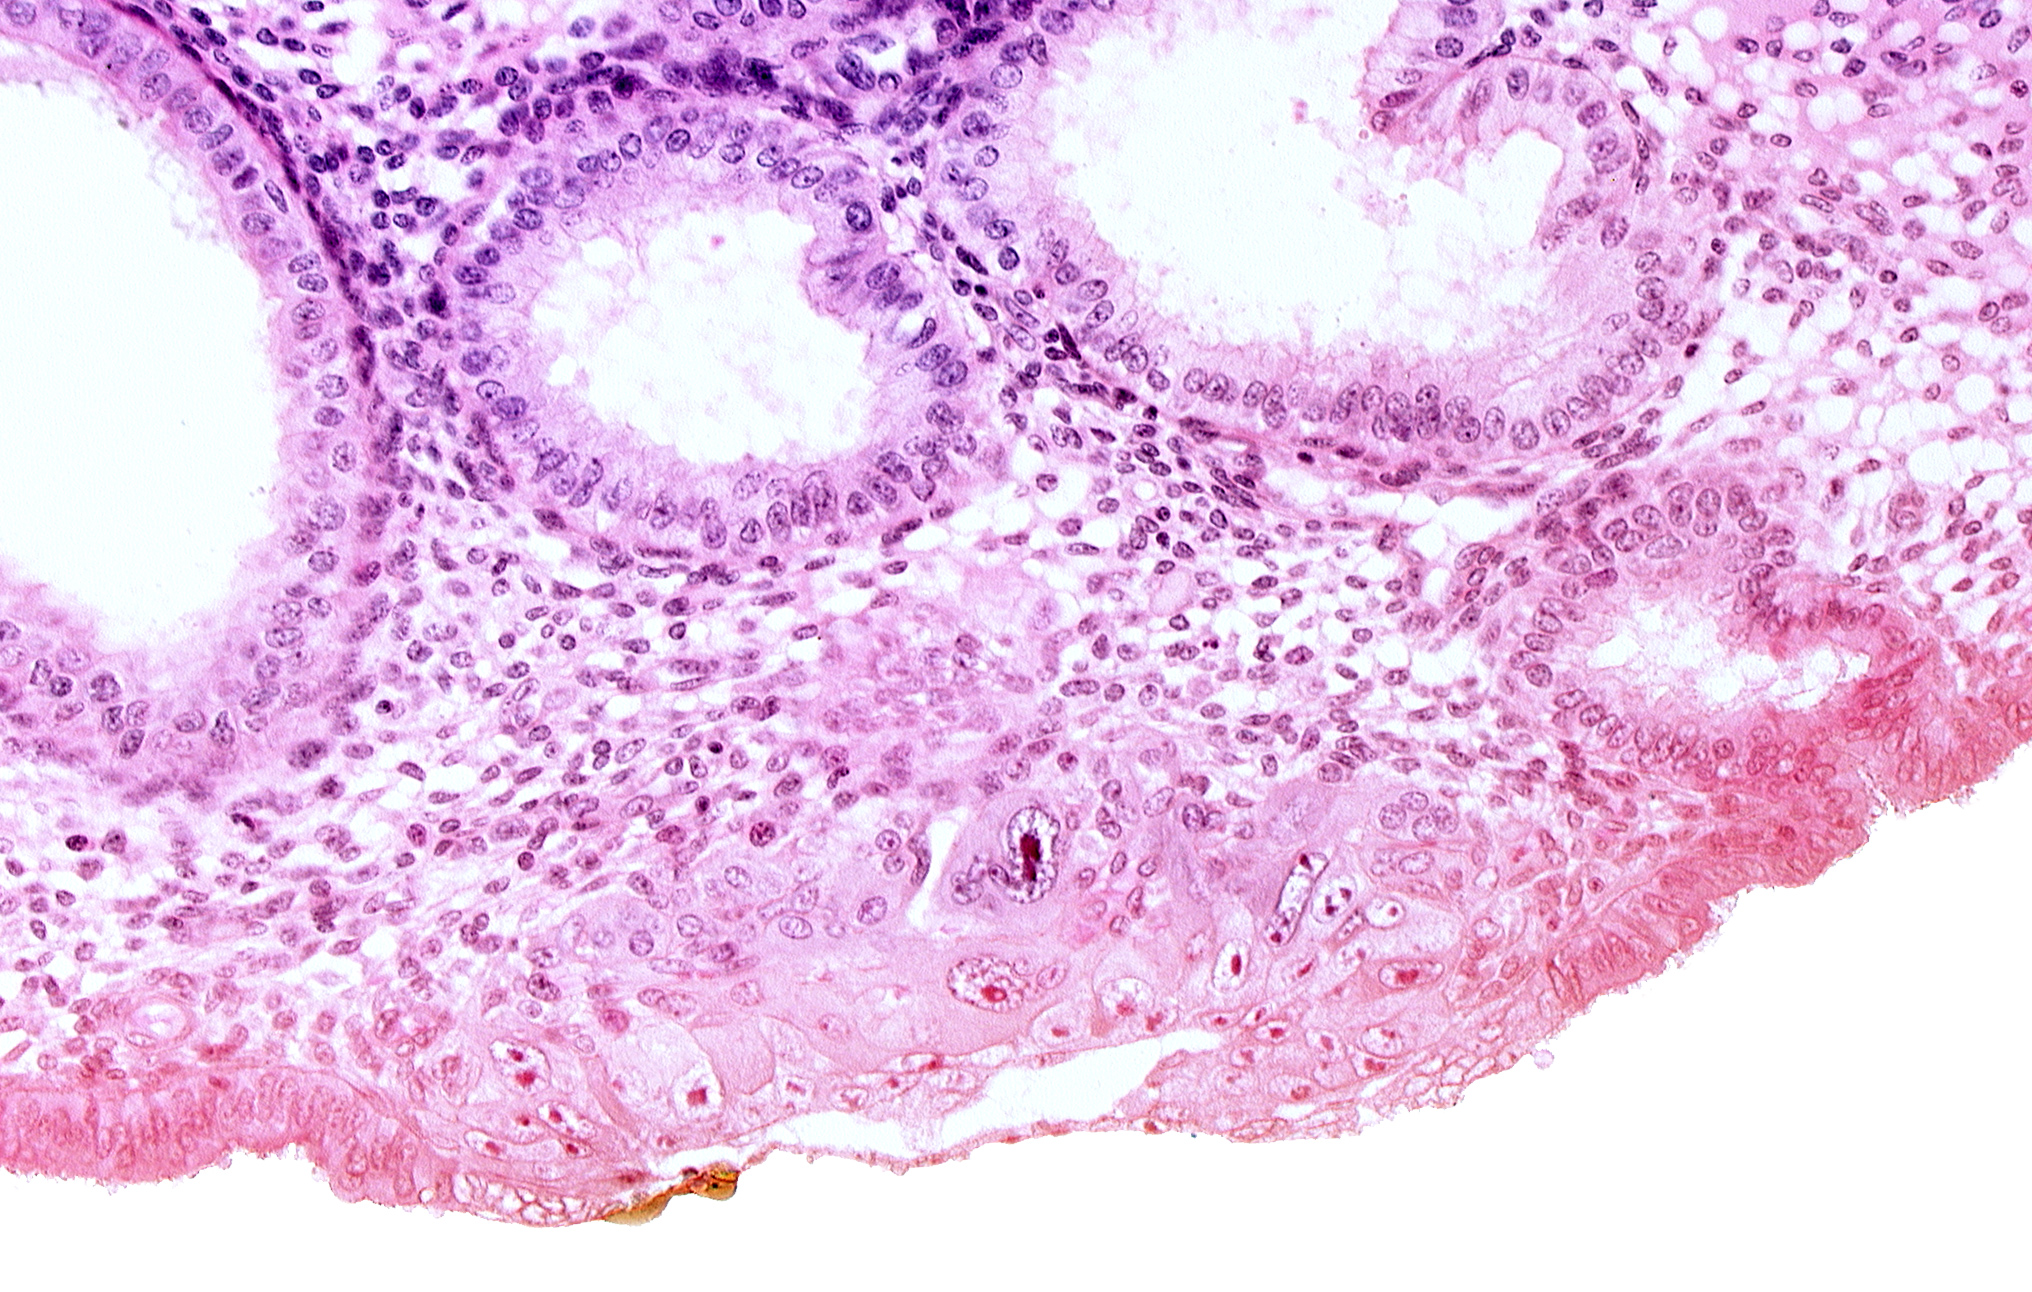

Carnegie Embryo #8020 | Location: 05-06-09

Keywords: blastocystic cavity (blastocoele), cytotrophoblast, edematous endometrial stroma (decidua), edge of endometrial gland, embryonic disc, endometrial sinusoid, membranous trophoblast at abembryonic pole, solid syncytiotrophoblast, syncytiotrophoblast / decidua interface

Source: The Virtual Human Embryo.